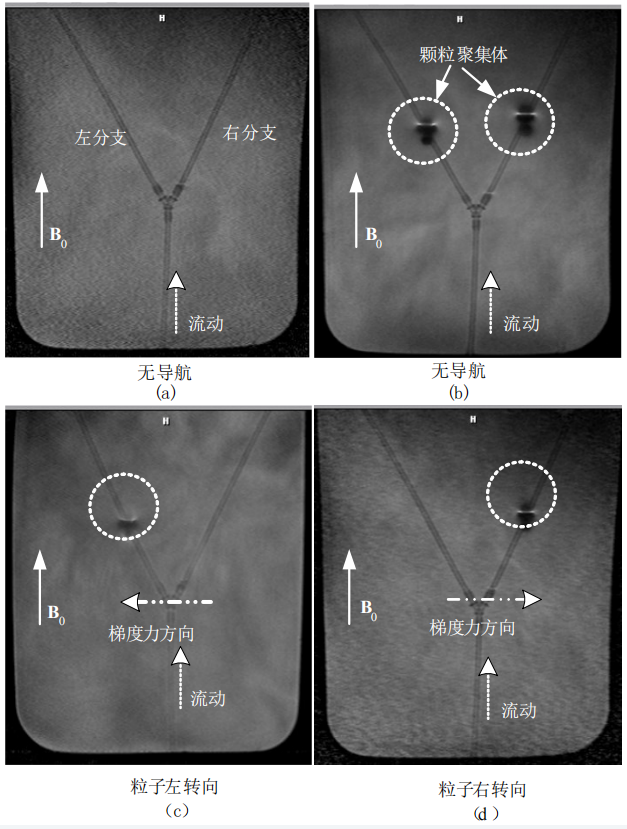

In the in vitro DFN-D experiment, the researchers validated the feasibility of particle manipulation. Following the predetermined plan, they moved the sphere to the distal position and then injected MMPs. The experiment employed a T1W-SE diagnostic imaging sequence to track the injected particle aggregates. The results showed that without navigation, the particle aggregates randomly entered sub-branches; whereas with the DFN-D system for navigation, the success rate of particle aggregates reaching both branches was 100%.

MR imaging of injected particle aggregates in the in vitro model: (a) shows MR imaging of the in vitro model before particle injection; (b) shows MR imaging of particle aggregates (injection count = 4) randomly entering different branches without navigation. In (c) and (d) (in each image, injection count = 2), the particle aggregates were successfully navigated to the left and right target branches, respectively.